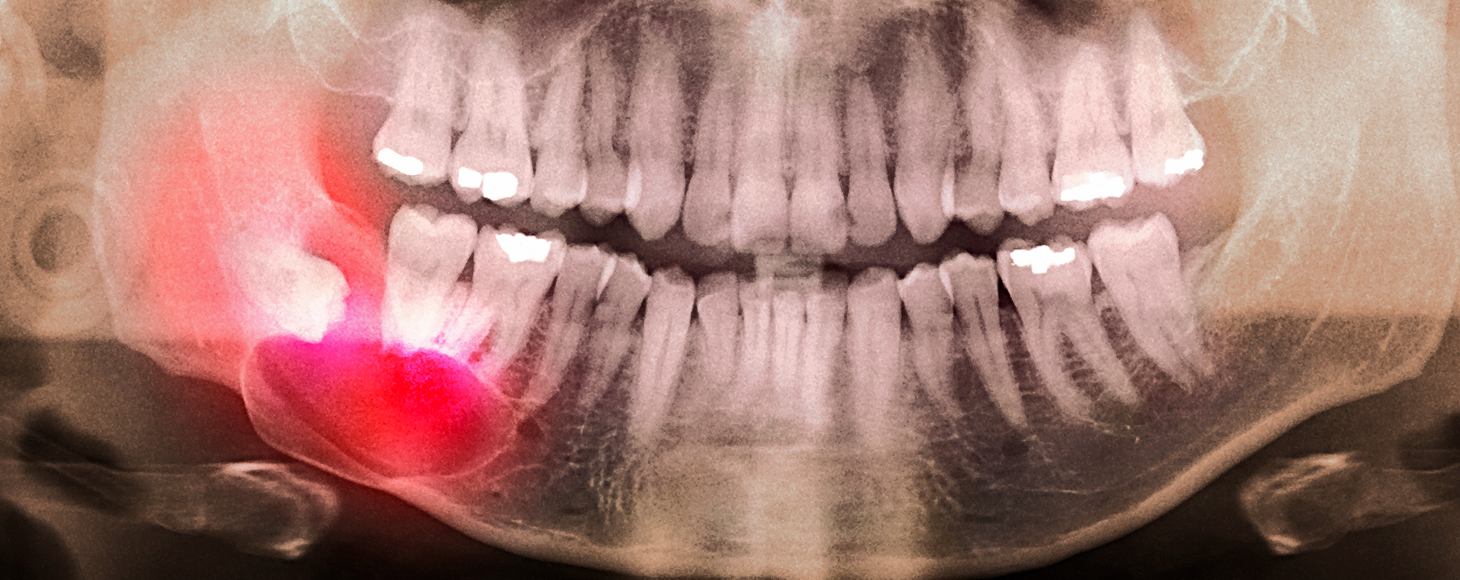

사랑니발치,

구강 건강을 위한 선택

잇몸 속에 묻히거나 비뚤게 난 사랑니를 안전하게 제거하는 시술입니다.

CT로 신경 위치를 확인해 통증과 부작용을 최소화합니다.

사랑니발치가 필요한 경우

사랑니가 잇몸 속에 일부만 나와 음식물이 자주 끼는 경우

잇몸 주변에 염증이 생기거나 통증이 반복되는 경우

옆 치아를 밀어 충치나 치아 이동이 생길 수 있는 경우

치아 배열이나 교합(물림)에 영향을 주는 경우

교정치료 전·후로 공간 확보가 필요한 경우